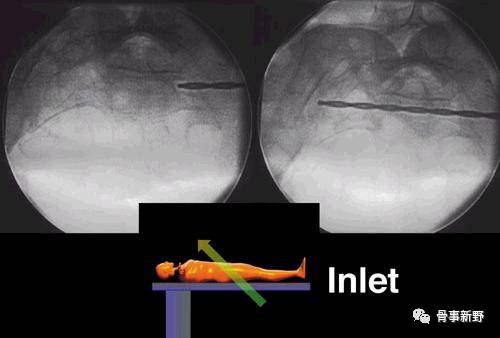

(2)透视:C形臂放在患侧,术中透视骨盆正位、入口位、出口位及侧位。

(3)复位:通过牵引或者复位器械协助复位,复位骨盆后部,使坐骨大切迹和双侧骶骨翼、髂骨皮质投影重叠,克氏针临时固定髂骨翼和骶骨翼。